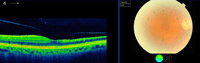

ORAR

Los pacientes con ORAR se quejan de disminución de AV monocular limitada a una zona del campo visual donde se encuentra la obstrucción. La fundoscopia revela edema retiniano en el territorio de la rama ocluida. Los émbolos pueden ser visibles hasta en el 66% de los casos

48,49 (

Figura 4 y

Figura 5).

Figura 4. Edema retiniano por oclusión de pequeña rama arterial temporal inferior en paciente con Síndrome de Susac.

Figura 5. Edema asociado a oclusión de rama arterial temporal inferior.